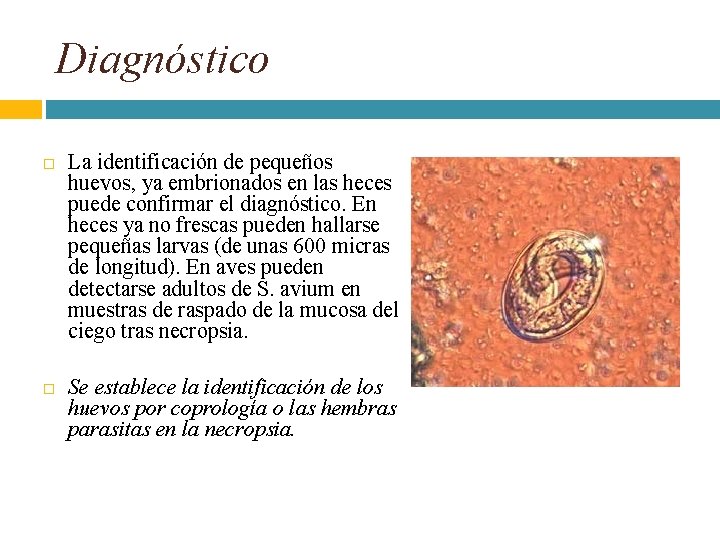

Diagnóstico La identificación de pequeños huevos, ya embrionados en las heces puede confirmar el diagnóstico. En heces ya no frescas pueden hallarse pequeñas larvas (de unas 600 micras de longitud). En aves pueden detectarse adultos de S. avium en muestras de raspado de la mucosa del ciego tras necropsia. Se establece la identificación de los huevos por coprología o las hembras parasitas en la necropsia.